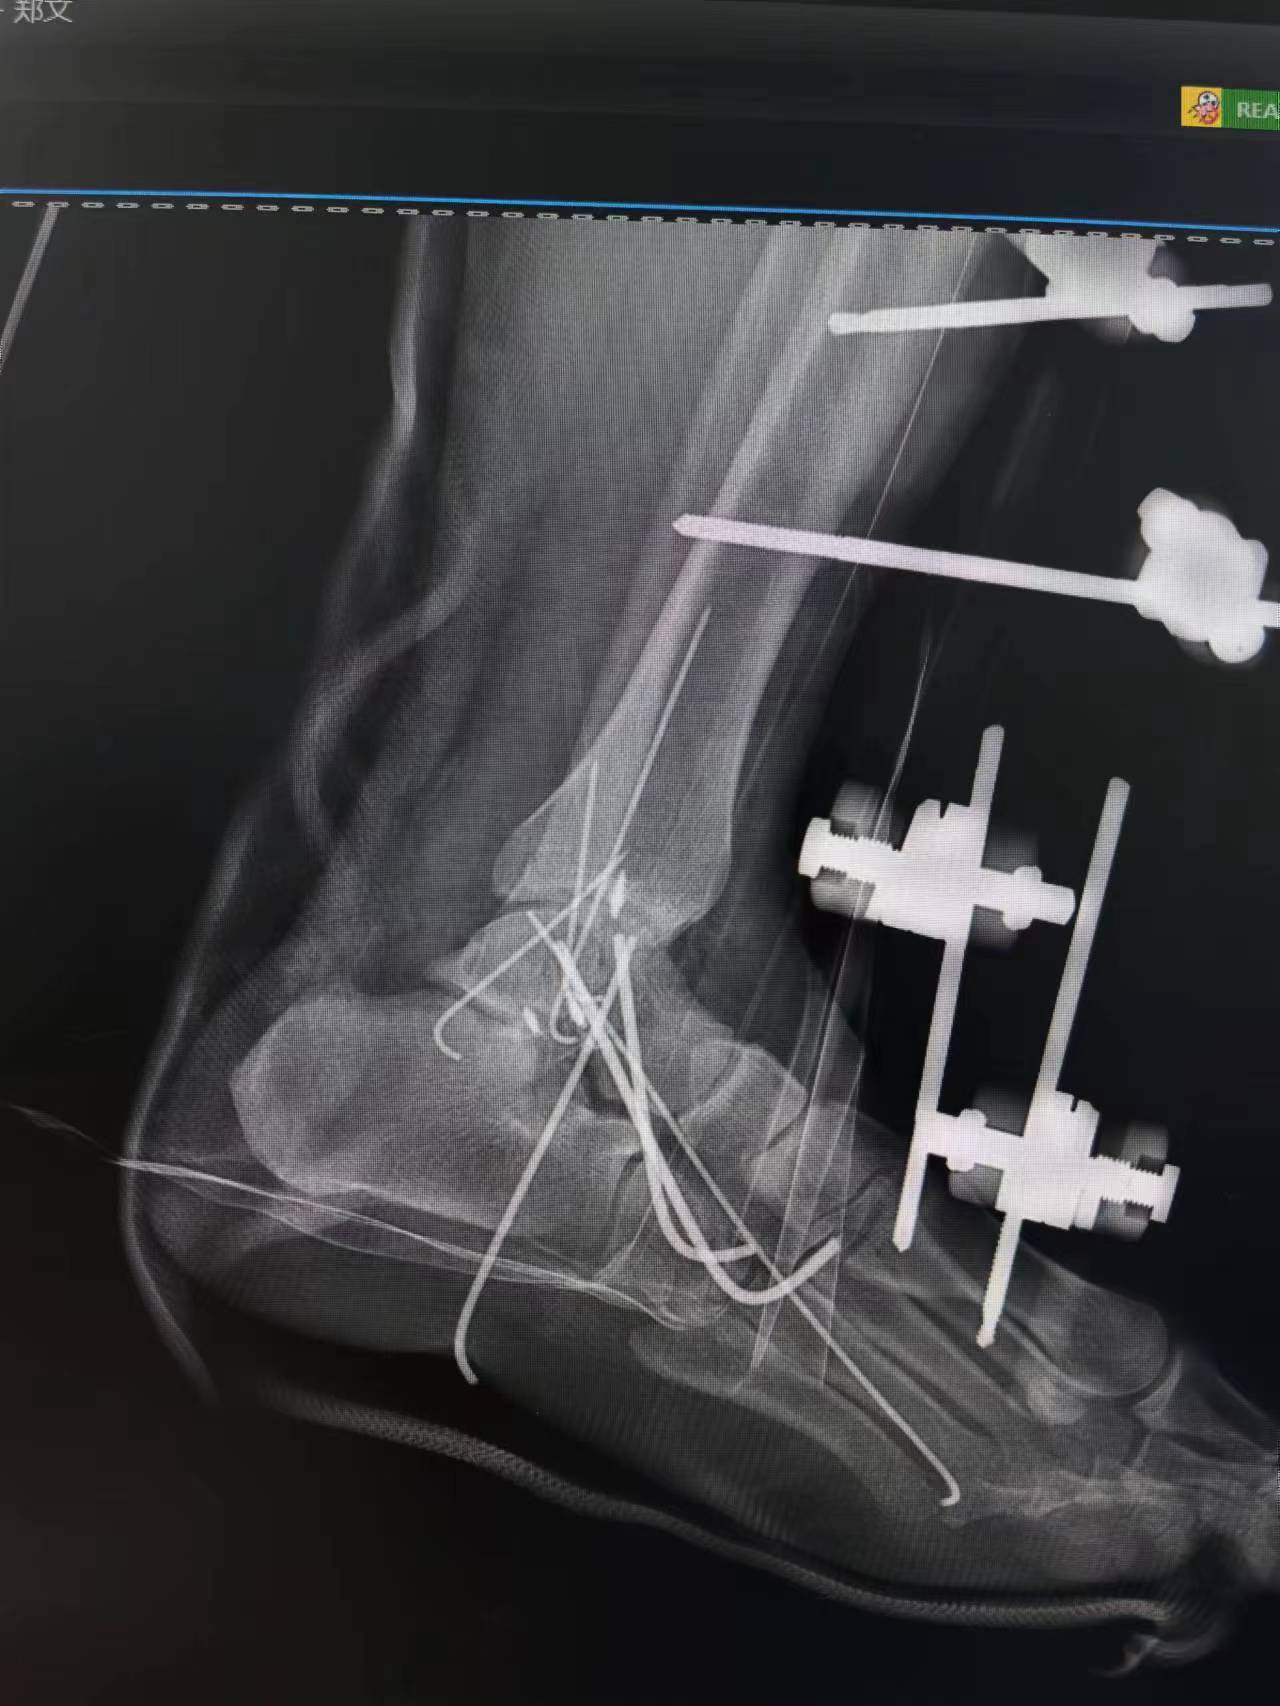

踝关节开放骨折脱位术前术后